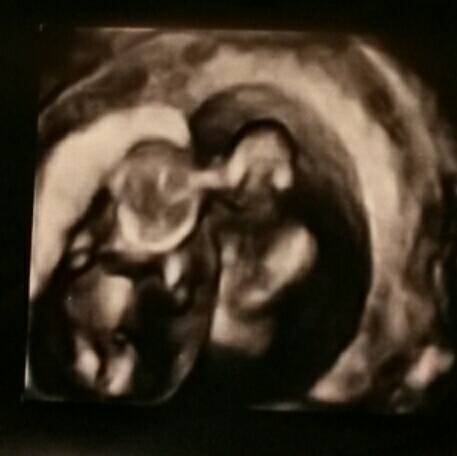

Kävimme tänään np-ultrassa. Kaksi kaverusta siellä edelleen jumppasi. Niskaturvotusta oli kummallakin alle 1mm ja muutenkin sikiöillä oli kaikki palikat paikoillaan. Kahden kätilön voimin selvittivät sitten, minkä tyyppinen raskaus on kyseessä ja molemmille löytyivät omat istukat ja kaikki muukin oli omaa. Eli paras mahdollinen tilanne tässä vaiheessa. Kokoa kaveruksilla oli sen verran, että vastaavat viikkoja 12+1 ja 11+6. Ihan viikkoja vastaavat ovat siis.

Saatiin mukaan ihan hirveästi kuvia ja ultrassakin meni aikaa toista tuntia. Olisi ruutua kyllä pidempäänkin vielä katsellut. Sen verran veikeän näköistä oli kaverien meno. Selvästi olivat jakaneet vuorot, että kun toinen lepää, toinen riehuu ja sitten vaihdetaan. Onneksi asennot olivat hyvät, että kätilö sai kaikki tarpeelliset mitat otettua.